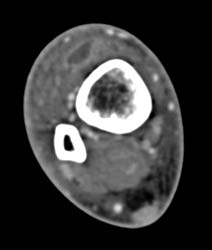

Bone Cyst Vs Fibrous Dysplasia